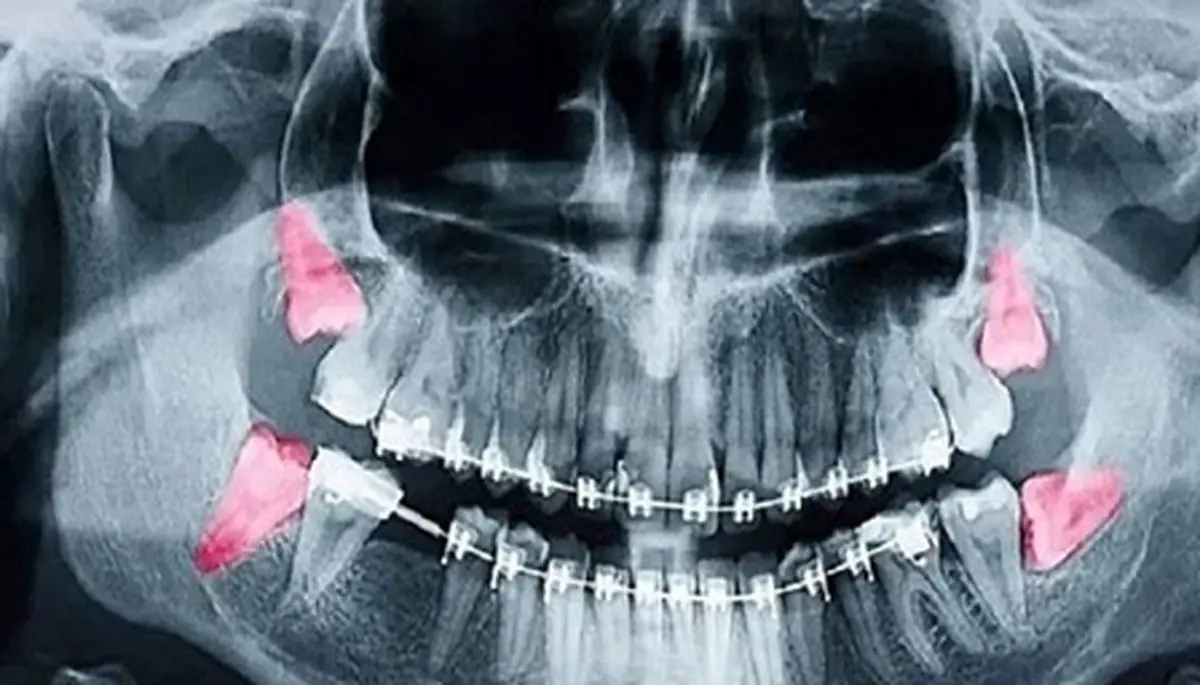

وی توضیح داد: میزان اشعه در رادیوگرافی‌های دندانی بسیار پایین است؛ برای مثال، میزان اشعه در یک رادیوگرافی داخل دهانی معمولی حدود ۰.۰۰۵ میلی‌سیورت و تصویر پانورامیک (OPG) حدود ۰.۰۲ میلی‌سیورت است که به ترتیب هزار و ۲۵۰ برابر کمتر از حد مجاز ۵ میلی‌سیورت در دوران بارداری است.

وی تصریح کرد: در تصویربرداری پانورامیک دندان (OPG)، استفاده از محافظ تیروئید توصیه نمی‌شود.

وی توضیح داد که تابش پرتو از پشت سر بیمار انجام می‌شود و قرار دادن محافظ می‌تواند سایه در نواحی چانه، ریشه دندان‌های قدامی یا فک پایین ایجاد کند؛ این موضوع کیفیت تصویر را کاهش داده و احتمال نیاز به تکرار عکس را افزایش می‌دهد که در نهایت میزان تابش اشعه را بالا می‌برد.